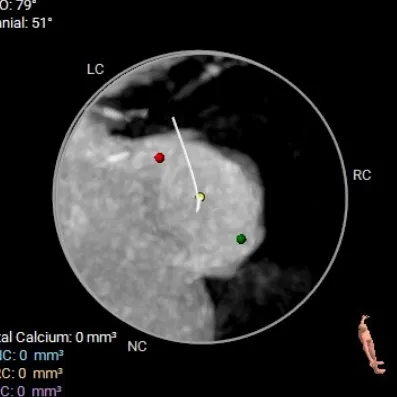

术前CT评估:TYPE 0型二叶瓣,瓣叶肥厚,前后交界粘连,瓣叶无明显钙化,双冠异窦,左冠开口高度约16.6mm,右冠开口高度约16.7mm。法式窦结构小,STJ高度约21.6mm,直径约24.4mm,升主动脉未见明显增宽,心脏角度约42°,左室大小尚可,心尖部可见局部心肌薄弱。

TYPE 0型二叶瓣,瓣叶肥厚,前后交界粘连,瓣叶无明显钙化

钙化积分:0mm³,无钙化